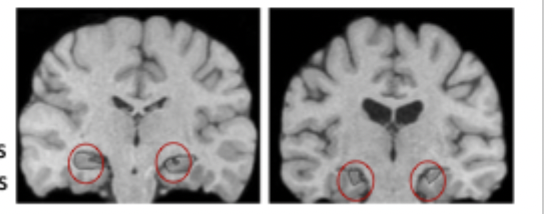

Where is peak atrophy is SD normally located compared to HM?

damage adjacent to hippocampus but still distinct